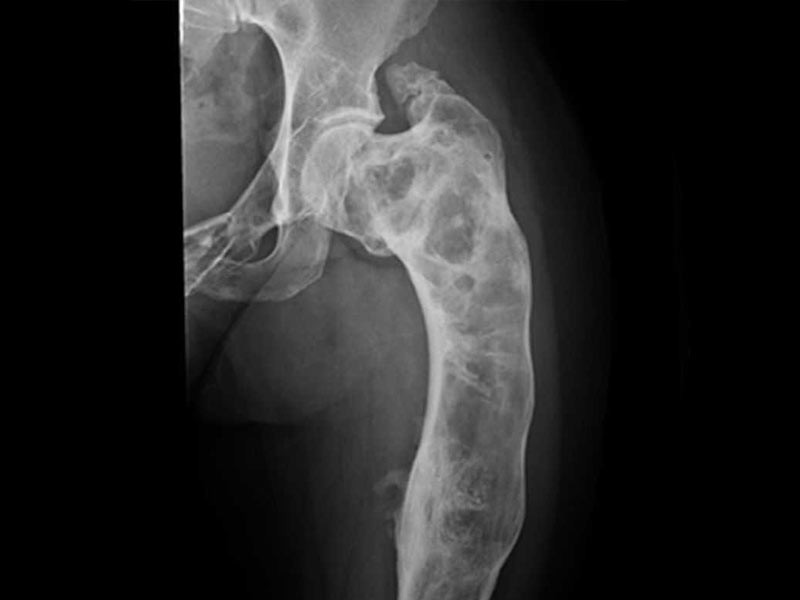

Простая костная киста, также известная как солитарная или ювенильная костная киста, представляет собой однокамерную полость внутри кости. Эта полость выстлана тонкой соединительнотканной оболочкой и заполнена прозрачной или желтоватой жидкостью. Чаще всего ПКК локализуется в длинных трубчатых костях, которые быстро растут: в 90–95% случаев это проксимальные (ближние к туловищу) отделы плечевой или бедренной кости.

Диагностика ПКК обычно не представляет сложностей для опытного специалиста. Основным и в большинстве случаев достаточным методом является рентгенография. На снимке простая костная киста имеет характерные признаки, которые позволяют отличить ее от других, в том числе злокачественных, образований.

Что врач видит на рентгенограмме:

- Четкие границы: полость имеет ровные, хорошо очерченные контуры.

- Центральное расположение: киста находится в центре костномозгового канала.

- Вздутие кости: кость в месте расположения кисты может быть несколько расширена.

- Истончение кортикального слоя: стенки кости, окружающие полость, выглядят тонкими.

- Отсутствие реакции надкостницы: нет признаков воспаления или агрессивного роста, характерных для злокачественных опухолей.

В некоторых сомнительных случаях, для уточнения размеров кисты, оценки состояния окружающих тканей или для дифференциальной диагностики с другими костными патологиями (например, с аневризмальной костной кистой) могут быть назначены дополнительные исследования: компьютерная томография (КТ) или магнитно-резонансная томография (МРТ). Биопсия (взятие образца ткани для анализа) при ПКК проводится крайне редко, только при атипичной рентгенологической картине.